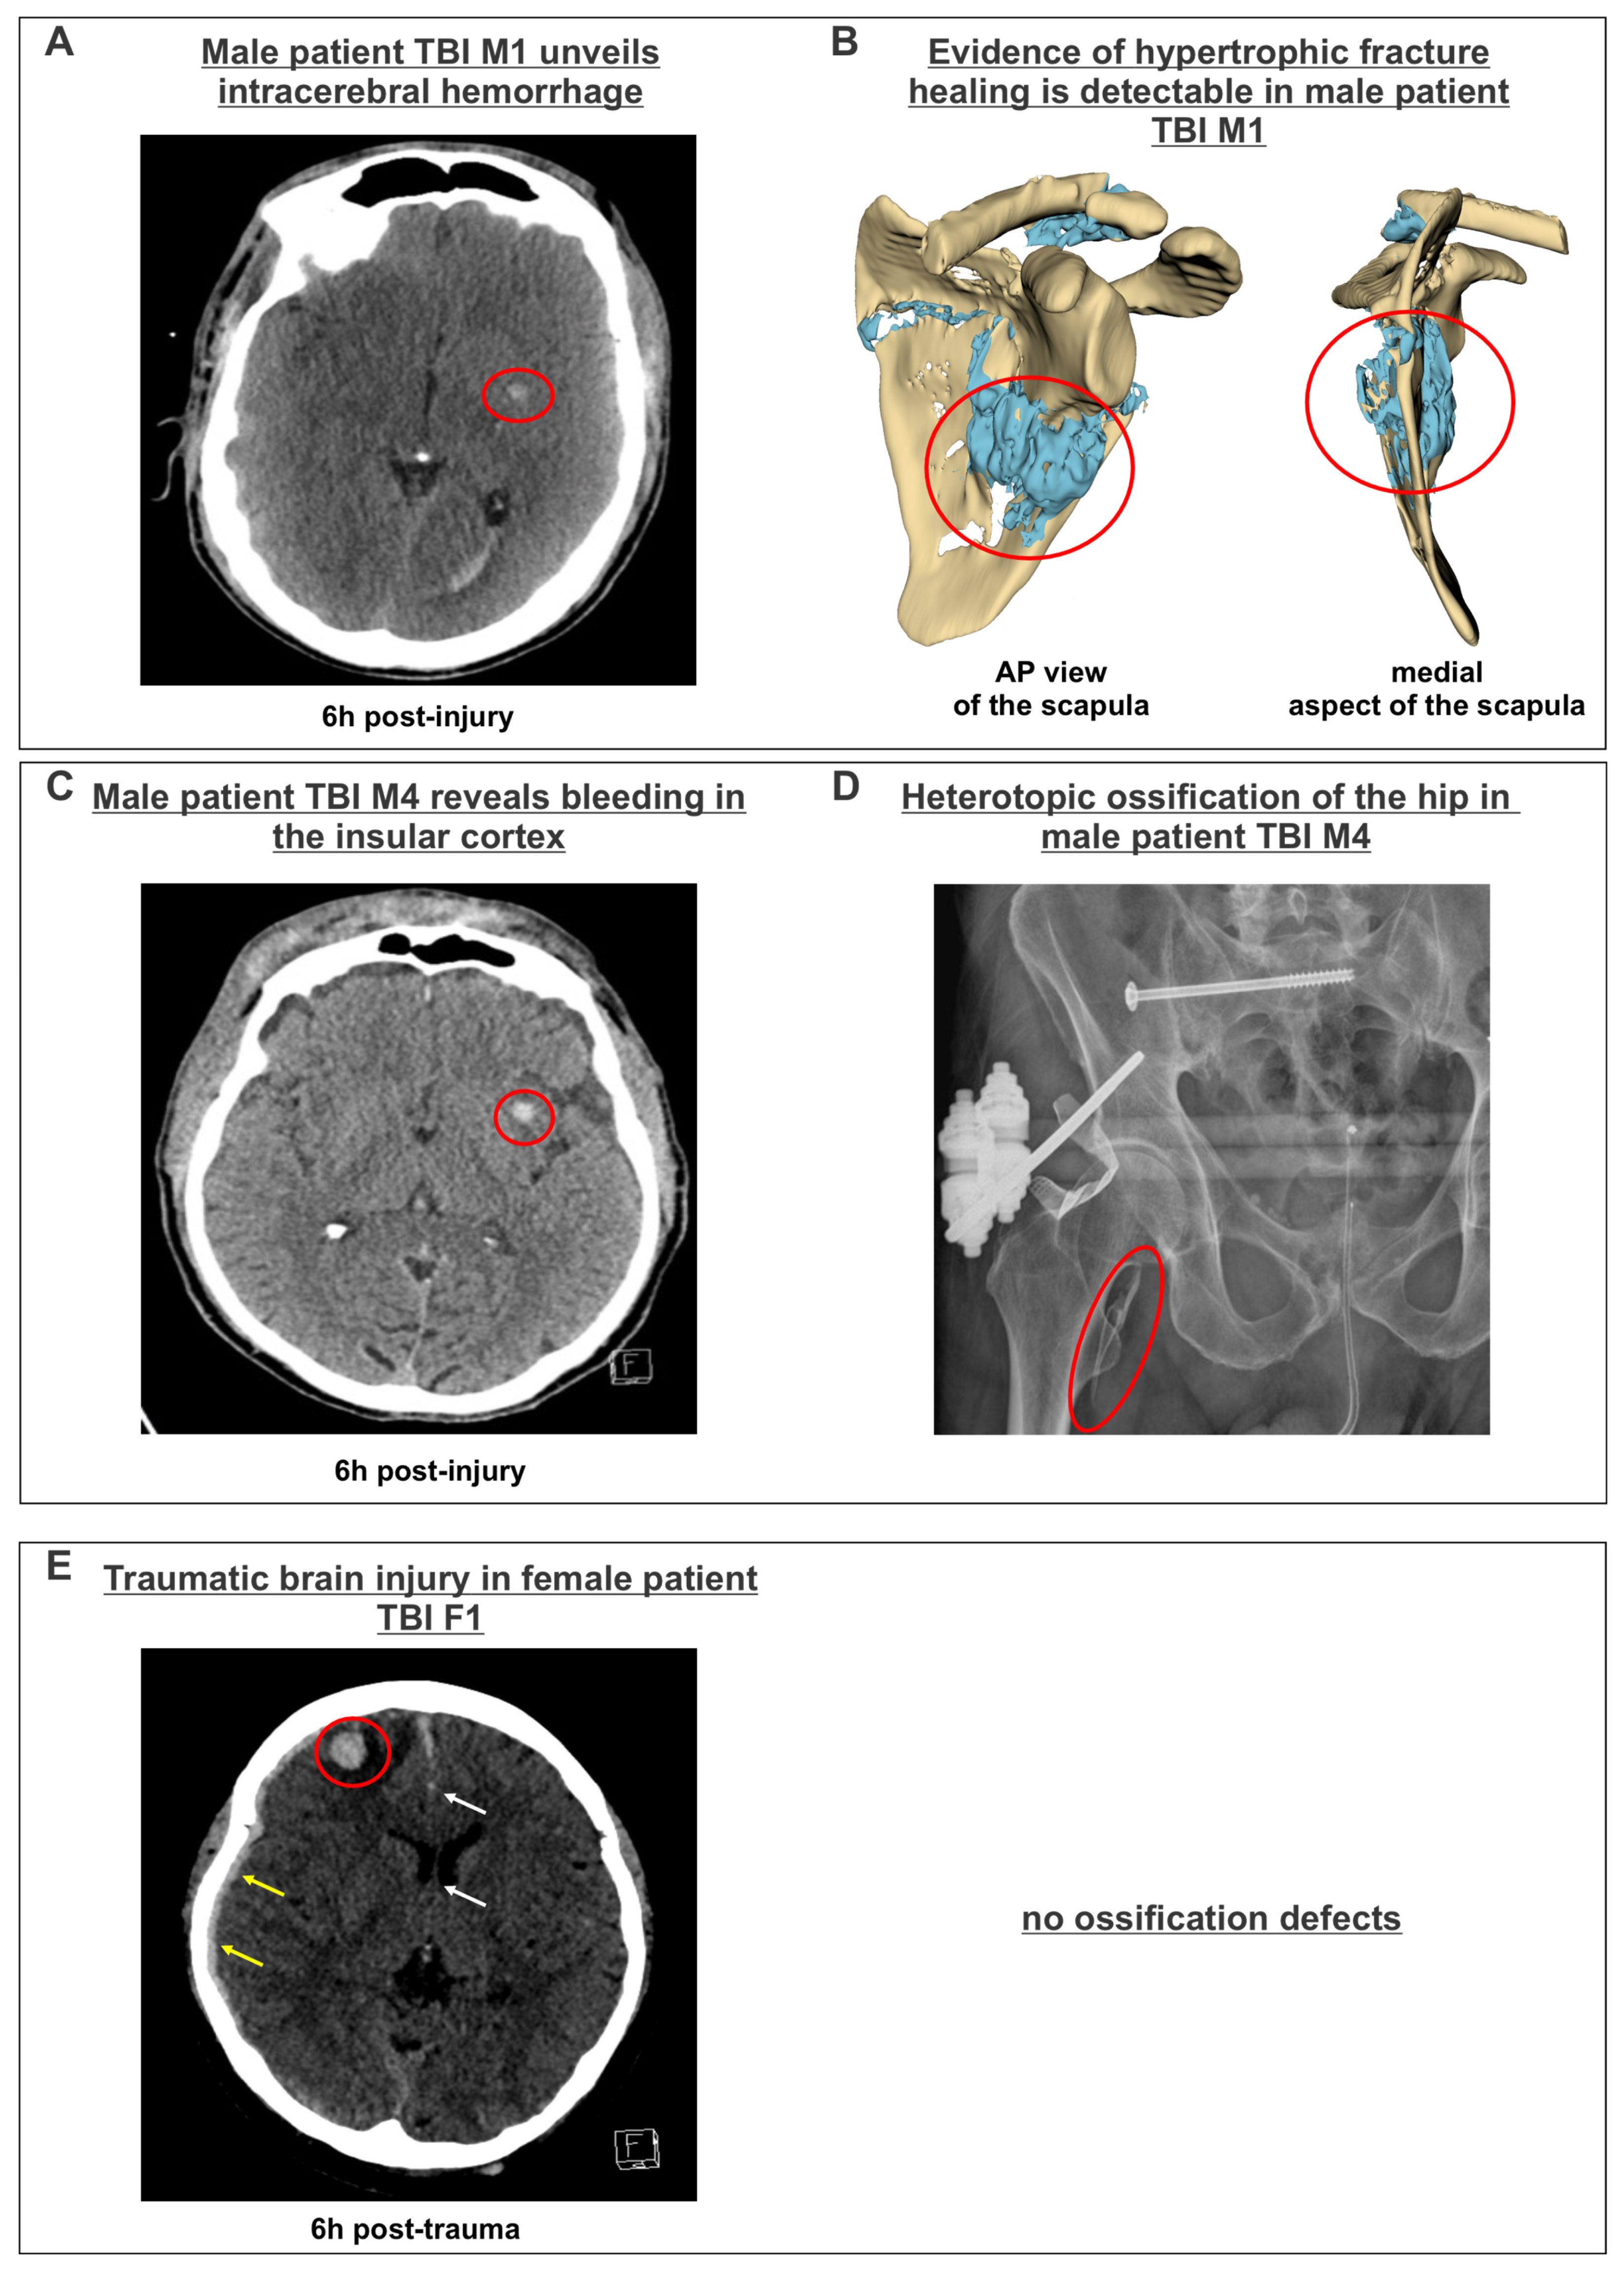

| TBI M1 | Male | 34 | TBI, cerebral hemorrhagic contusion, chest trauma, extremity trauma | 29 | 1.470 | 3 | +++ (hypertrophic fracture healing) |

| TBI M4 | Male | 77 | TBI, cerebral hemorrhagic contusion, chest trauma, extremity trauma, spinal trauma | 34 | 3.930 | 7 | +++ (heterotopic ossification) |

| TBI F1 | Female | 53 | TBI, basilar skull fracture (occipital condyle fracture), subdural hematoma, cerebral hemorrhagic contusion | 9 | 5.060 | 3 | − |